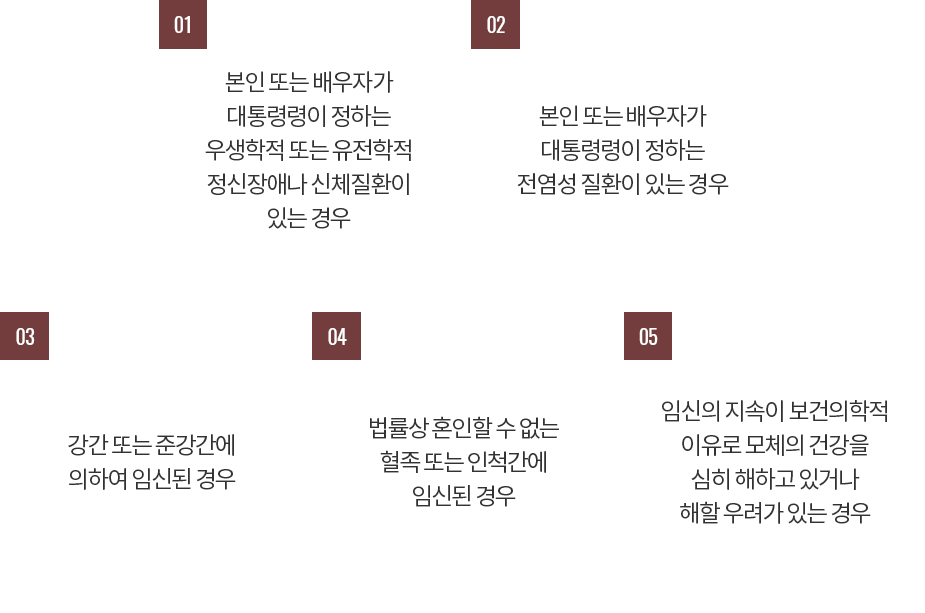

우리나라의 경우 인공 임신중절수술은 엄격히 모자보건법에 명시된 몇몇 허용사유에 국한되어 수술이 가능합니다.

우리나라의 경우 인공 임신중절수술은 엄격히 모자보건법에 명시된 몇몇 허용사유에 국한되어 수술이 가능합니다.

우리나라의 경우 인공 임신중절수술은 엄격히 모자보건법에 명시된 몇몇 허용사유에 국한되어 수술이 가능합니다.

우리나라의 경우 인공 임신중절수술은 엄격히 모자보건법에 명시된 몇몇 허용사유에 국한되어 수술이 가능합니다.

우리나라의 경우 인공 임신중절수술은 엄격히 모자보건법에 명시된 몇몇 허용사유에 국한되어 수술이 가능합니다.

우리나라의 경우 인공 임신중절수술은 엄격히 모자보건법에 명시된 몇몇 허용사유에 국한되어 수술이 가능합니다.

모자보건법 제14조에 의거하여 해당사유에 따라 임신중절수술이 가능한 사례는 다음과 같습니다.